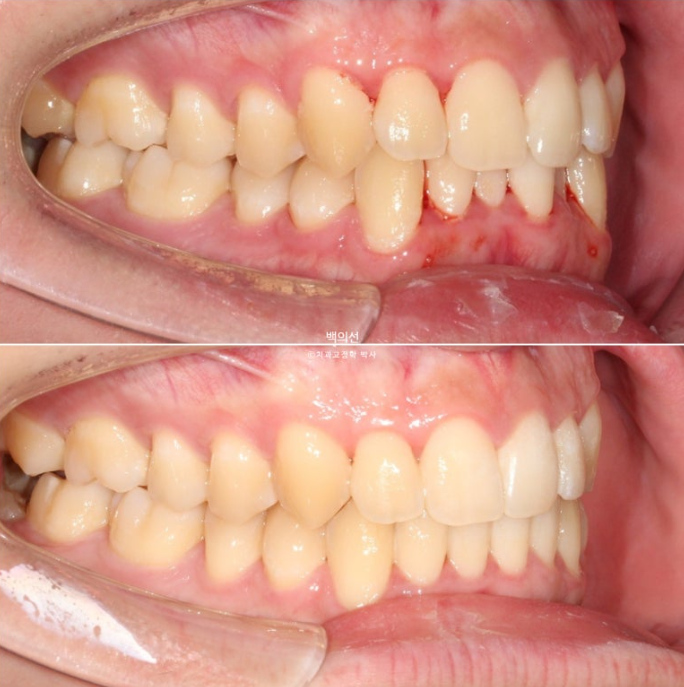

25.02~25.08

교정 후 아래 앞니 잇몸 라인 높낮이가 자연스럽게 맞아진 것이 보입니다.

치아 높이가 교정으로 맞아지면 잇몸라인은 자연스럽게 맞아집니다.